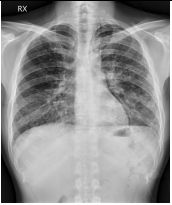

2. A 27-year-old woman had productive cough for one month.